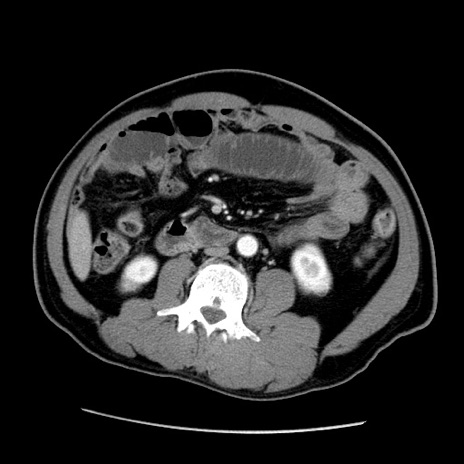

症例22(横断像)

【症例】50歳代男性

【主訴】腹痛

【現病歴】AVMからの被殻出血のため回復期リハ病棟入院中。 本日午後3時頃急に下腹部痛が出現した。

【既往歴】AVM、被殻出血、虫垂炎、高血圧

【身体所見】意識晴明、左半身不全麻痺、会話の理解は良好、36.5°C、腹部:膨隆、全体に板状硬、下腹部正中に圧痛点あり、反跳痛-、筋性防御不明、右下腹部にope scar

【データ】WBC 9400、CRP 0.06